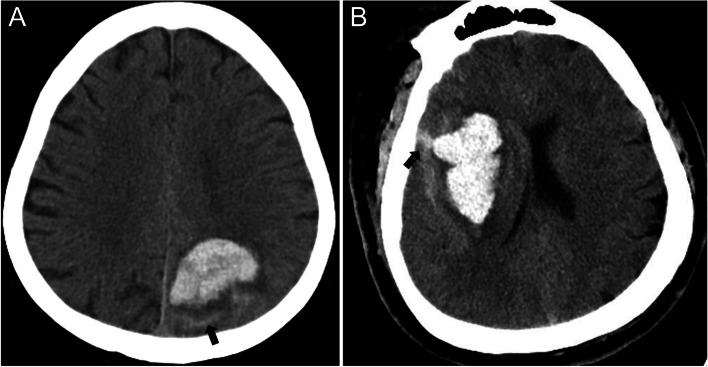

All patients underwent a baseline NCCT imaging scan according to standardized parameters. The coordinating center centrally gathered digital imaging in uncompressed DICOM formats. Two experienced investigators analyzed these imagings separately, who were blinded to other data. SAHE was defined as the presence of any blood in the subarachnoid space (Fig. 1). Furthermore, hematoma volume was calculated by the ABC/2 method. Once there was some uncertainty about the judgment of imaging data, other different experts would further determine the result.

Fig. 1.

Intracerebral hemorrhage (ICH) with subarachnoid extension on baseline computed tomography. A Lobar ICH with subarachnoid extension (arrow). B Deep ICH with subarachnoid extension (arrow)